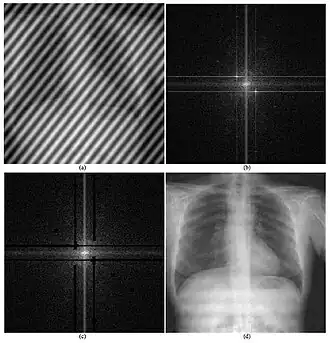

An example of how image processing can be applied to radiography.

An example of how the 2D Fourier transform can be used to remove unwanted information from an X-ray scan